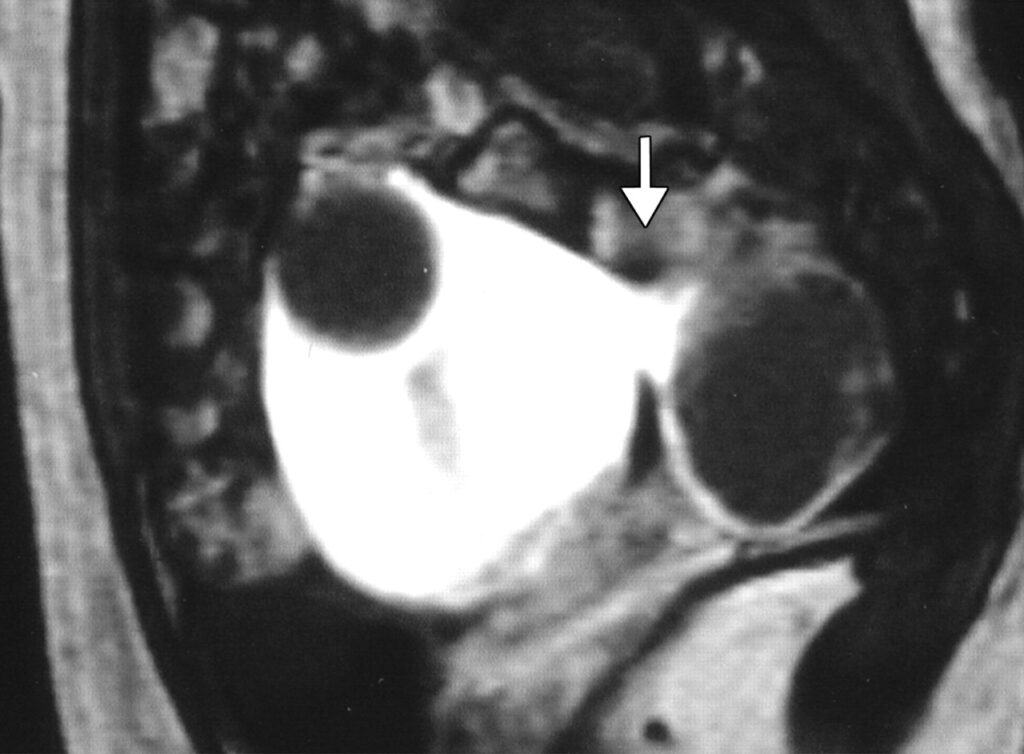

- UFE has a success rate of 90%, providing relief from fibroid symptoms like heavy menstrual bleeding, pelvic pain, and increased urinary frequency (Fig. 2)

Nearly all patients who qualify for surgery are also candidates for UFE, and UFE is covered by all major insurance providers, including Medicare and Medicaid.